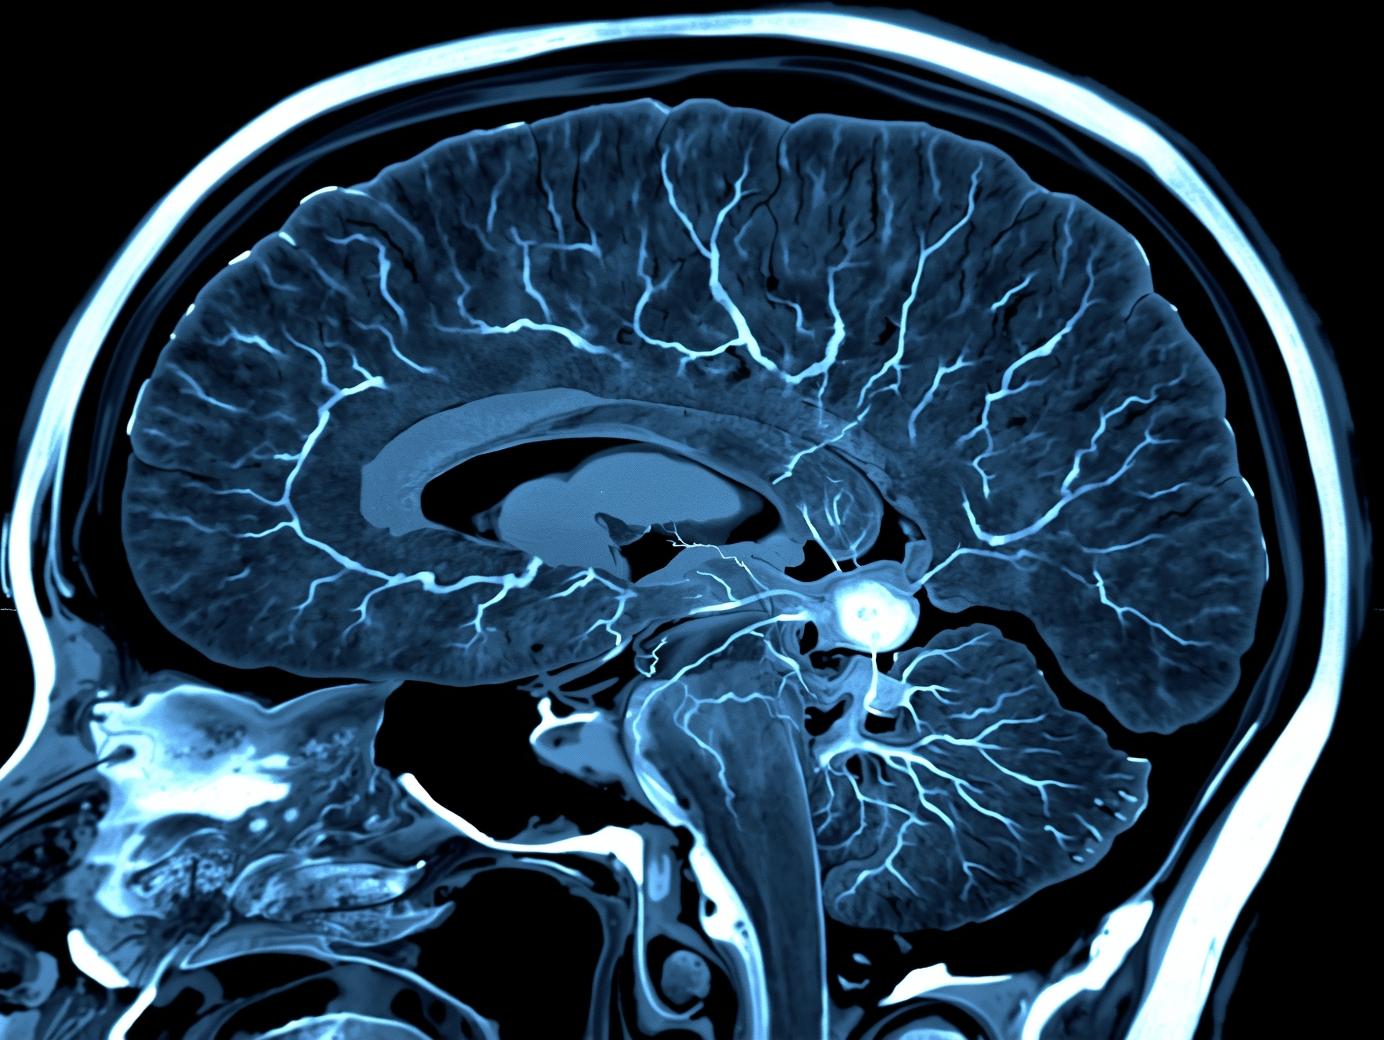

下垂体腫瘍は、多くが良性で、ゆっくりと進行します。ただし、腫瘍の位置やホルモンへの影響により、体にさまざまな症状が現れることがあります。

ラトケ嚢胞は、胎生期に下垂体が形づくられる過程で生じるラトケ嚢の遺残からできる、良性の嚢胞性病変です。

頭蓋咽頭腫は、下垂体の近くにできる良性の脳腫瘍です良性腫瘍に分類されますが、周囲の大切な組織と強くくっついていることがあり、治療は決して容易くありません。また、再発することもあるため、手術後も長期的な経過観察が必要です。

脳腫瘍には数多くの分類があります。大きくは「良性」と「悪性」に分けられ、どちらかによって治療の方針が変わります。良性の脳腫瘍は、手術で取りきることで治ることも多くあります。